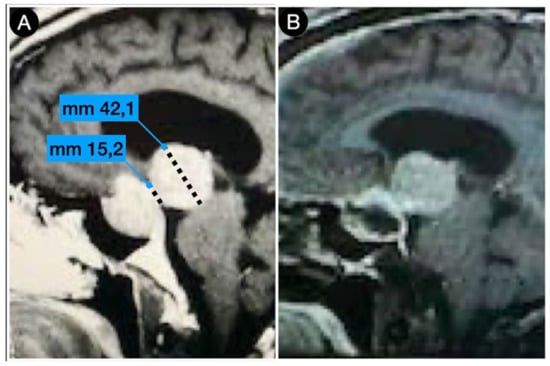

2.5. Anatomy of The Sellar Diaphragm

Case #1: Infradiaphragmantic Tumor with Middle Fossa Involvement through the Cavernous Sinus

- Harel, E.; Cossu, G.; Daniel, R.T.; Messerer, M. Relationship with the diaphragm to predict the surgical outcome in large and giant pituitary adenomas. Front. Surg. 2022, 9, 962709. [Google Scholar] [CrossRef]

- Campero, A.; Martins, C.; Yasuda, A.; Rhoton, A.L. Microsurgical Anatomy of the Diaphragma sellae and its Role in directing the Pattern of Growth of Pituitary Adenomas. Neurosurgery 2008, 62, 717–723. [Google Scholar] [CrossRef] [PubMed]

- Micko, A.S.G.; Keritam, O.; Marik, W.; Strickland, B.A.; Briggs, R.G.; Shahrestani, S.; Cardinal, T.; Knosp, E.; Zada, G.; Wolfsberger, S. Dumbbell-shaped pituitary adenomas: Prognostic factors for prediction of tumor nondescent of the supradiaphragmal component from a multicenter series. J. Neurosurg. 2022, 137, 609–617. [Google Scholar] [CrossRef]